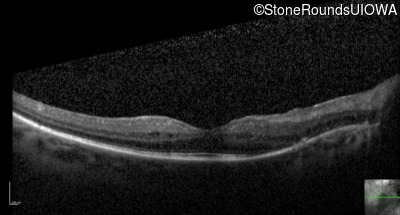

Optical Coherence Tomography - Left - 20/32

Exemplar / OCT Stack

OCT Stack